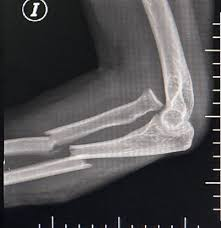

Mecanismo de lesion de esta fractura

Mecanismo INDIRECTO

Caida sobre la mano extendida con el codo en flexion

Se produce por avulsion de una parte de la apofisis por una contraccion del triceps

Mecanismo DIRECTO

Golpe directo al codo por caida o trauma

Tipo de fractura en la clasificacion de Mayo

1a (no desplazada, no conminutada)

2a (Desplazada estable, no conminutada)

3b (Desplazada inestable (por la luxacion) y conminutada)

Tratamiento de esta fractura

Conservador

Inmovilizar con yeso o ferula a 45-90°, inicio gradural de movilizacion a las 4 semanas

Obenque con clavillos de kirschner y alambre

Trtamiento de esta fractura

Fijacion con placa y tornillos (por multifragmentada)